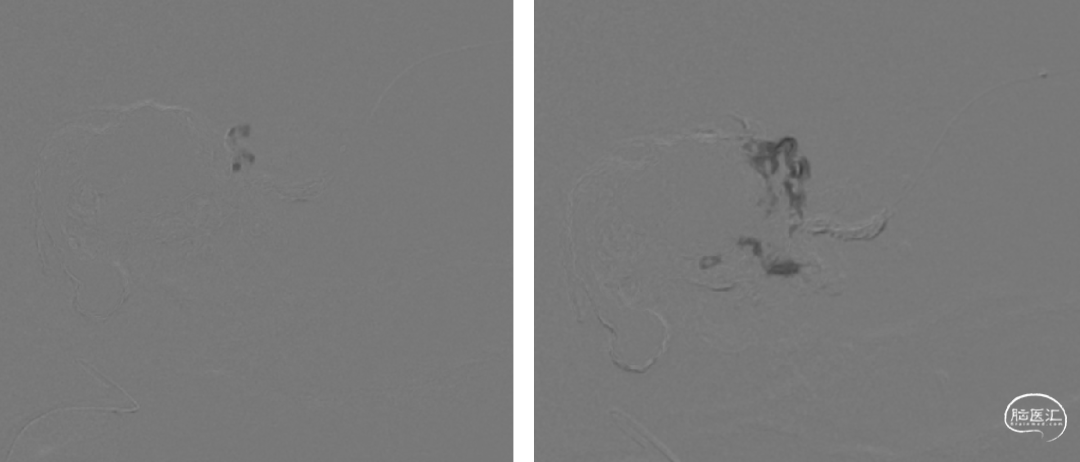

7个月前第一次静脉入路栓塞

术后即刻造影